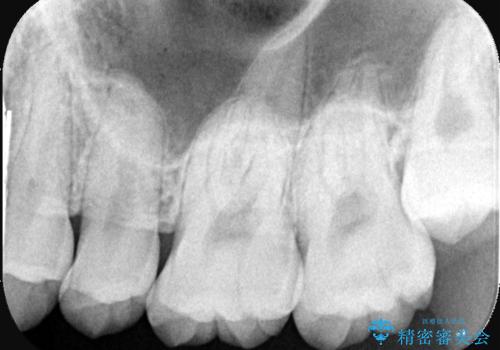

左上一番奥の歯の頬側に実質欠損を伴う虫歯が存在したため、セラミックインレーでの治療となりました。

上顎左側第二大臼歯頬側面から遠心面、咬合面にもう蝕が波及していたためアンレー形態となりました。